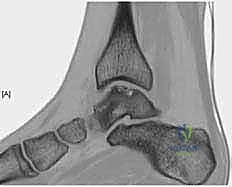

- الأشعة السينية (X-rays): تُستخدم كخطوة أولى لاستبعاد الكسور العظمية الكبيرة والتهاب المفاصل المتقدم. في بعض الأحيان، يمكن رؤية "ظل" أو كيس عظمي يشير إلى وجود آفة.

- التصوير بالرنين المغناطيسي (MRI): هو المعيار الذهبي (Gold Standard) لتشخيص OLTs. يُظهر الرنين المغناطيسي الغضروف بدقة عالية، ويحدد حجم الآفة، عمقها، وحالة العظم تحت الغضروفي (مثل وجود وذمة عظمية - Bone Marrow Edema).

- الأشعة المقطعية (CT Scan): يطلبها الدكتور هطيف أحياناً للحصول على خريطة ثلاثية الأبعاد دقيقة للعظم، مما يساعد في التخطيط الجراحي وتحديد حجم الرقعة العظمية المطلوبة للزرع.